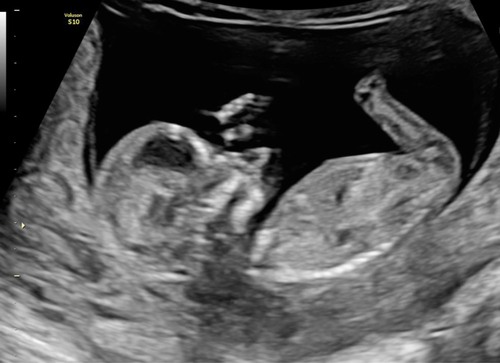

Vandaag de 13 weken echo gehad van onze tweeling. Alles was goed en ze lagen er als fotomodelletjes bij dat we binnen een half uur weer buiten stonden 😅. Zo verliefd en blij ❤️ (bovenste foto is kindje 1 aan het drinken)